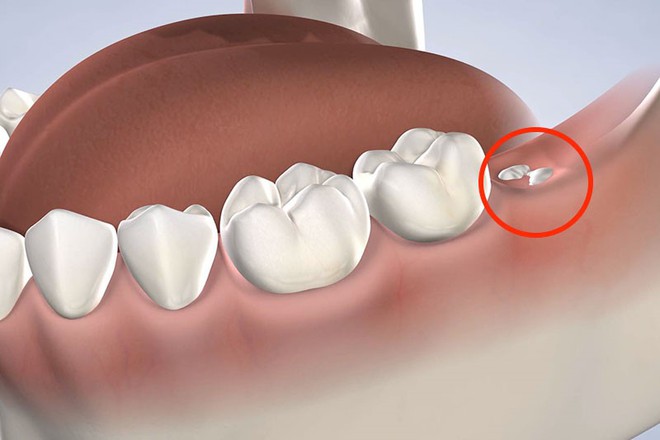

Vì mọc khi xương hàm đã cứng cáp, có niêm mạc, mô thì phủ dày bên trên nên khi răng khôn xuất hiện chúng sẽ thiếu không gian để phát triển. Cũng vì vậy mà những chiếc răng khôn thường mọc ngầm, bị lệch lạc hay đâm cả vào chiếc răng bên cạnh vì thiếu chỗ. Do đó quá trình mọc răng khôn khiến chúng ta bị đau đớn âm ỉ, khó chịu vô cùng. Những người bị nặng còn bị đau buốt, viêm nhiễm.

Vì sao luôn mọc ở chỗ không ai muốn, gây đau đớn nhưng răng khôn lại được đặt cái tên “thông minh” như vậy? Đáp án thật ra rất hợp lý - Ảnh 2.

Răng khôn được coi là biểu tượng đánh dấu cho sự trưởng thành, chín chắn và khôn lớn hơn của con người